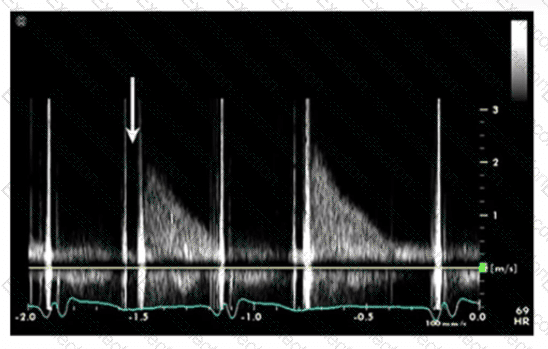

Which phase of the cardiac cycle is indicated by the arrow on this image?